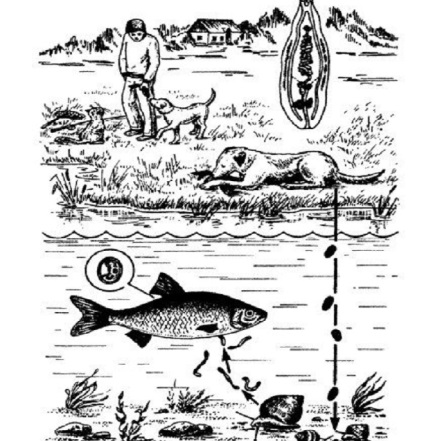

Kórokozók Opisthorchisfelineus könnyen terjed át a nagy kiterjedésű az élet, és egy nagy lista élőlényre ez a parazita és gyorsan szaporodik.

- Fish. Friss nem kezelik termikusan vagy sózott halat okozhatnak betegséget, mert mindkét betegség a test ideális az ilyen típusú paraziták.

- Háziállatok. Érdemes megjegyezni, hogy a betegség fedezték fel egy macska. Pet kutya is jutalmazzák host betegség.

parazita maga úgy néz ki specifikusan :. kifelé egy kis féreg hossza 0,18 cm és szélessége 0,02 cm az elülső részben van 2 tapadókoronggal, amely a parazita tulajdonít a fogadó és mozgatja a testen keresztül. Hátul bélféreg herék ez: 2 réteg az 5 és 4 lapátok. A közepén a test a méh, amely sötétebbé a többi féreg.

Terjed a tojásokat, amelyek megtalálhatók a méhbe. Tojás sárga vagy sárgás-szürke fehér szabálytalan ovális hosszú és 30 mikron.

Opisthorchiasis gyakran él és parazita az epehólyag és a csatornák tulajdonos: férfi, kutya, macska. Fontos szempont az ilyen típusú megértéséhez életciklusa férgek egy többfázisú a fejlesztési, attól függően, hogy melyik gépen is megfertőzi. Például egy ember vagy egy kutya tojás esik a vízbe, ahol ő eszik kagylók és kis halak, akkor szabadul fel és jut a nagyobb halak, vagy ragadozó megeszi együtt az áldozat, ami után van egy fertőzés, és egy nagy hal válik hordozót és képes megfertőzni egy személy , macska, kutya. Ezután a ciklus ismétlődik csak gyorsabb, mert a féreg képes alkalmazkodni egy adott környezetben.